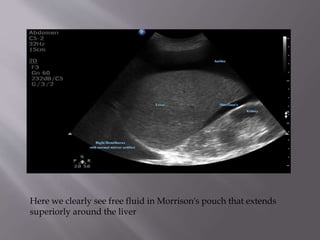

Here we clearly see free fluid in Morrison's pouch that extends

superiorly around the liver

Here we clearlysee free fluid in Morrison's pouch that extends superiorly around the liver